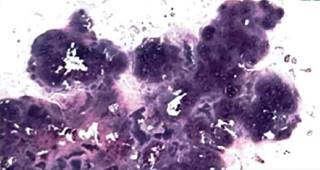

Masculino de 54 años, que consulta por dolor, bloqueos al momento de flexionar y extender la rodilla izquierda de dos años de evolución sin antecedentes de trauma. Se evalúa marcha dolorosa acompañado de edema y dolor en rodilla izquierda. La resolución del caso se realizó mediante cirugía: artroscopia de rodilla con resección completa de la condromatosis sinovial (Figuras 1 a 3).